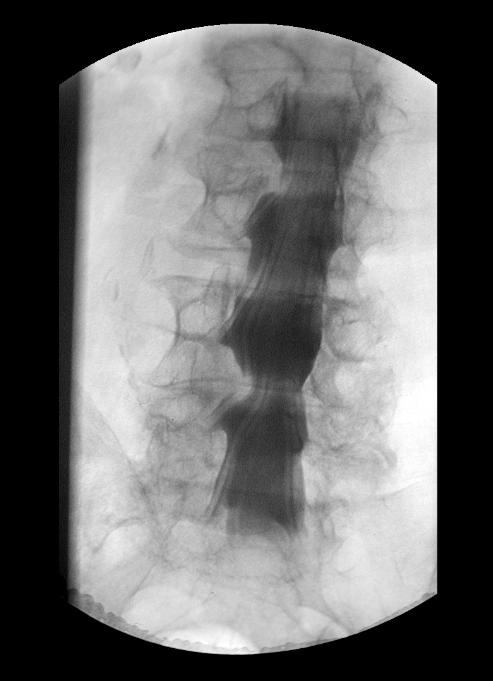

Die Myelographie ist ein Verfahren zur Darstellung des Nervenwasserkanals der Wirbelsäule. Dieser kann beispielsweise bei einem Bandscheibenvorfall, durch Tumoren oder Verschleisserkrankungen eingeengt sein.

Unter Röntgendurchleuchtung wird an der Lendenwirbelsäule ein jodhaltiges Medikament gespritzt, welches alle Nervenfasern des Rückenmarks sichtbar macht.

Wichtig ist die Myelographie vor allem dann, wenn Symptome zu klären sind, die unter Belastungssituationen der Wirbelsäule auftreten.